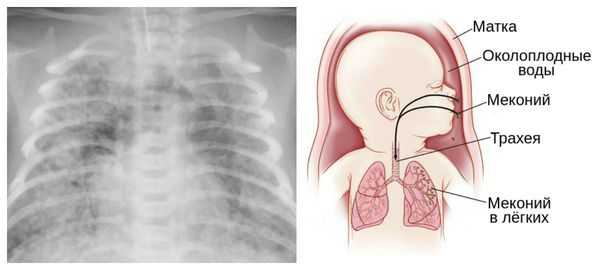

Пролонгацией физиологической беременности считают увеличение сроков гестации до 290-294 дней при отсутствии признаков старения плаценты и перезрелости плода. При истинном перенашивании беременность заканчивается рождением перезрелого плода с морфофункциональными изменениями в плаценте. К признакам переношенной беременности относится уменьшение количества околоплодных вод, отсутствие первородной смазки, сморщивание и сухость кожи ребенка, появление в водах примеси мекония, вследствие чего их цвет становится сероватым или зеленоватым.

Картина УЗ-исследования при переношенной беременности характеризуется уменьшением общего объема и полным отсутствием «передних вод», отсутствием хлопьевидных включений сыровидной смазки в амниотических водах, наличием в водах мекония. Допплерография маточно-плацентарного кровотока определяет признаки старения плаценты, которая в полной мере не обеспечивает питание и кислородное снабжение плода: петрификаты в плаценте, уменьшение ее толщины, сниженную интенсивность фетоплацентарного и маточно-плацентарного кровотока. Все эти данные указывают на перезрелость плода и испытываемую им гипоксию. Уменьшение ЧСС плода (менее 110-120 уд. в мин.) или увеличение (свыше 160 уд. в мин.) по результатам кардиотокографии подтверждают нарушения в состоянии плода.

Для диагностики переношенной беременности может применяться методика цервикальной амниоскопии - эндоскопического исследования характера околоплодных вод через неповрежденную стенку плодного пузыря. Зеленоватый цвет вод, свидетельствующий о примеси мекония, указывает на внутриутробную гипоксию плода. Амниоскопия может проводиться только в ситуациях, когда шейка матки мягкая и приоткрыта для введения прибора.

Опасности переношенной беременности для ребенка заключаются в возможной гипоксии плода и асфиксии новорожденного, развитии поражений головного мозга, получении родовых травм, аспирации мекония и околоплодных вод. Состояние детей, родившихся от переношенной беременности, отягощается выраженной желтухой, гормональными кризами, инфекционными поражениями кожи, неврологическими нарушениями. Впоследствии они нередко отстают от нормального физического и психического развития.

Из-за снижения кровотока в почках плода выделение мочи значительно уменьшается, развивается маловодие. Также изменяется характер околоплодных вод: они теряют прозрачность, становятся мутными, приобретают желтоватый или зеленоватый оттенок из-за примеси мекония — первых фекалий ребёнка.

Осложнения перенашивания беременности

Для плода большую опасность представляет асфиксия (острая гипоксия) и отслойка плаценты. Нехватка кислорода внутри утробы стимулирует плод выполнить несвоевременные дыхательных движения. Они приводят к заглатыванию вод и возможному воспалению лёгочной ткани — пневмониту. Если в водах есть примесь мекония (первородного кала), то велика вероятность мекониальной аспирации — проникновения содержимого кишечника новорождённого в его лёгкие.